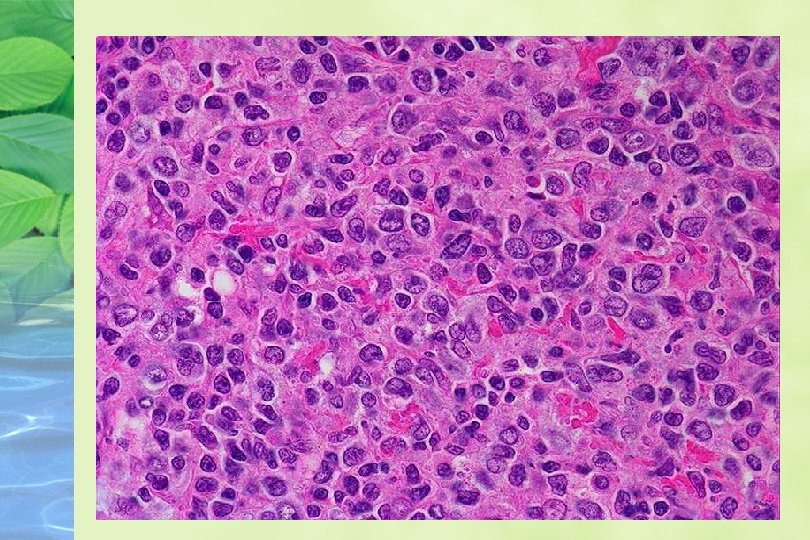

HALLAZGOS HISTOLOGICOS GANGLIO: Arquitectura reemplazada por un patrón difuso o vagamente nodular % pequeño es típicamente nodular Células neoplásicas monótonas , linfocitos pequeños de contorno nuclear irregular, cromatina condensada , nucleolo pequeño, mitosis 19/ 20 hpf